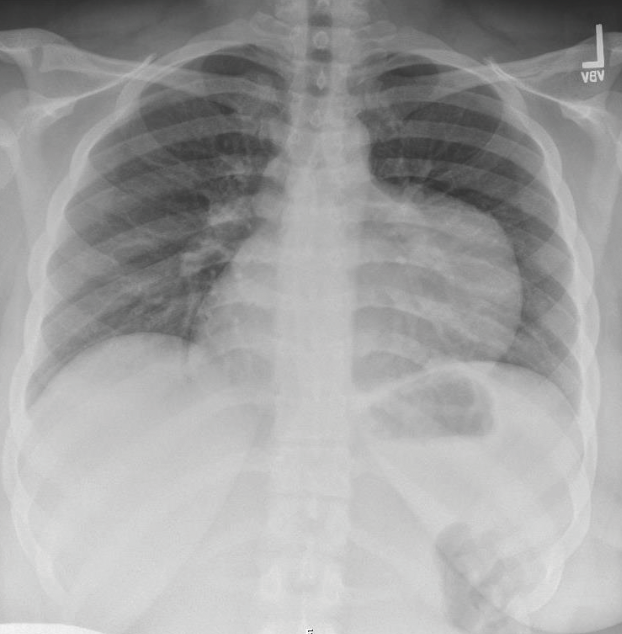

<p>A 16-year-old girl presented to the pediatric emergency department complaining of sudden-onset chest pain that had started a few hours ago. </p>